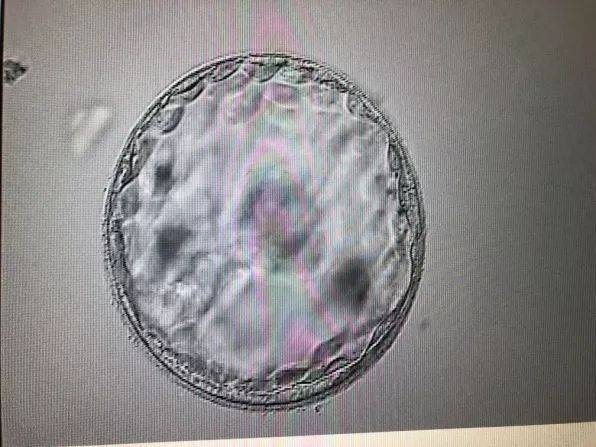

受精卵着床是指受精卵在子宫内壁上附着的过程。这一过程通常发生在受精后的第6-12天。在这个过程中,受精卵会释放一系列激素,促使子宫内膜发生变化,为胚胎的附着提供适宜的环境。